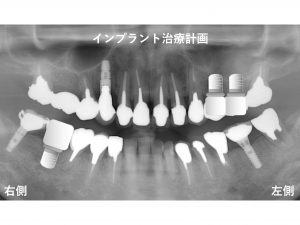

本日のテーマは、

インプラント治療計画の変更:神経のない歯のトラブル です。

以下が初診時です。

下顎右側奥から2番目の歯が欠損している患者様です。

初診時にはすでにインプラントが複数行われています。

以下のような治療プランを計画しました。

下顎右側に1本

上顎左側に2本

のインプラントです。